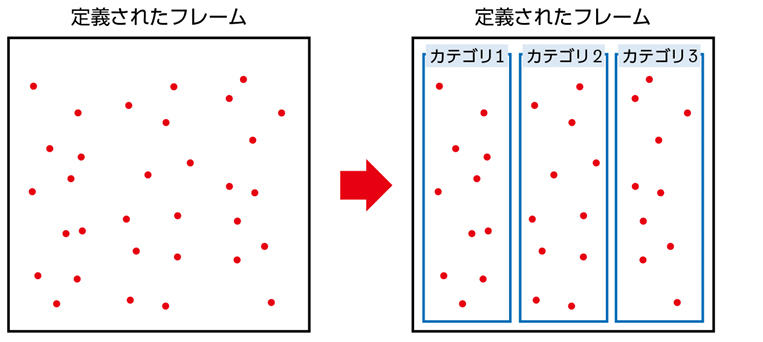

▶ 分析的診断推論とは,論理的に選び出した,可能性のある複数の診断を検討することである。膨大な数の疾患の中から可能性のある診断群を選び出すためには,まず疾患全体を含む空間の中に,「この内側に確実に真の診断がある(この外側には確実に真の診断はない)」という「枠」を置くことが必要である。仮にそうせずに推論を進めるのであれば,広大な空間内から行き当たりばったりで疾患を選んでいくことになる。これは要するに直観的診断の繰り返しであり,システム1が磨かれていなければ当たるも八卦,当たらぬも八卦で診断にたどり着けるかどうかわからない。

▶ 疾患全体という空間内に診断の可能性を限定する「枠」(フレーム)を置くことは,分析的診断の必要条件となる重要な一歩である(図2)。これを筆者は「フレーミング」と呼ぶ。

▶ もう少し進めると,フレーミングとは「患者のプレゼンテーションを,抽象的・一般的な医学用語の連なりからなる問題に変形させること」である。こうして定義された問題によって,「可能性のある疾患の範囲を決める枠組み(鑑別のフレーム)」ができる。患者の問題を,そこに拠って鑑別を考えられる形で定義するという意味で,筆者は「問題定義」という言葉も使う。ちょっと砕けた表現をするなら,「〇〇という『くくり』で鑑別を考える」という,「くくり」を決めることだ。